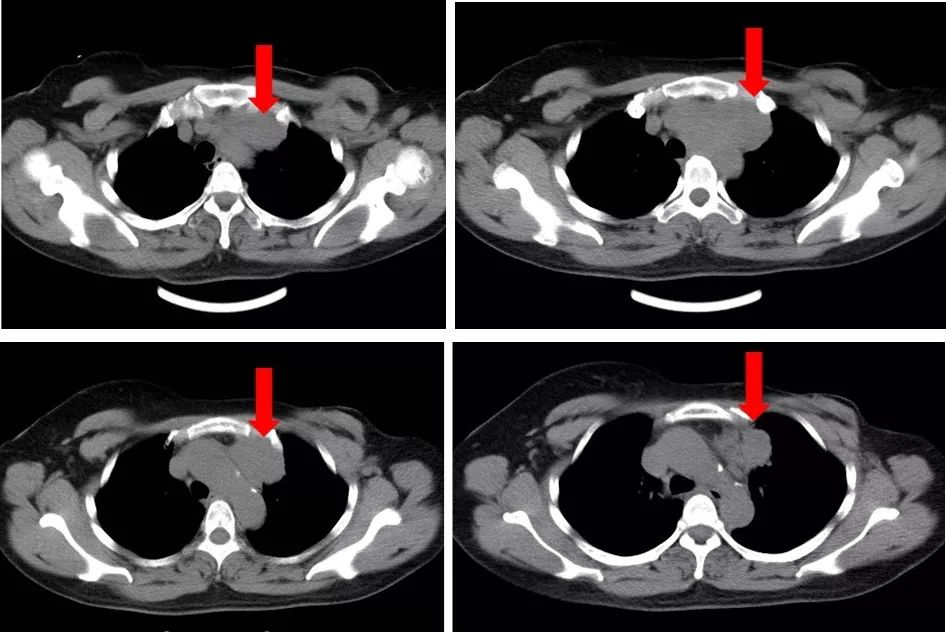

2017年1月12日门诊复查。左锁骨上窝可触及一大小约2.0×2.0cm肿大淋巴结,质略硬,活动度差。左颈部浅静脉怒张、左胸壁浅静脉曲张。右乳未触及肿物,双侧腋窝未触及肿大淋巴结。门诊彩超示:左侧锁骨上窝探及多个低回声结节,大的2.0*0.9cm,边界清楚,形态规整,皮髓分辨不清,诊断为左侧锁骨上窝多发肿大淋巴结。入院进一步复查,肺、脑、骨、肝未见远处转移征象。循环肿瘤细胞数0个/7.5mL外周血。2017年1月12日行胸部CT平扫示:前上纵隔左侧见一软组织密度影,部分边界欠清,最大截面约7.2cm×2.9cm。

图1. 胸部CT平扫